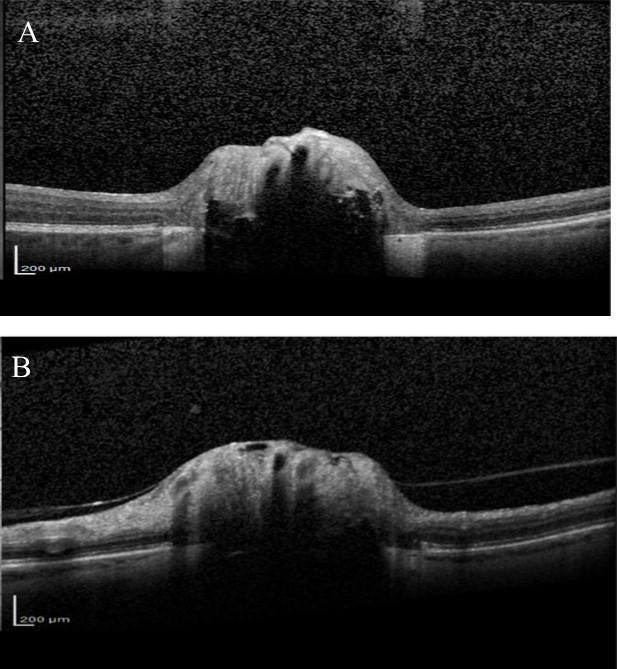

Over the next 6 months she felt the deterioration in vision in right eye had stabilised but complained that the vision in her left eye was gradually worsening. Visual acuity remained good but visual field testing confirmed a deterioration showing there had been a marked decline in the left eye visual field with MD deterioration from -9.59 to -24.01(Figure 4). Blood tests were taken for common Leber’s hereditary optic neuropathy mutations, which were negative. Vitamin B12 and folate levels were within normal range. Fundus fluorescein angiography (FFA) was also performed, looking for possible associated anterior ischaemic optic neuropathy (AION), but no evidence of late leakage was found. OCT examination of the RNFL was also performed and showed significant thinning in both eyes (Figure 5). Average RNFL thickness was only 57 um in the right eye but measured 87 um in the left, although the inferotemporal sector was outside normal limits in the left eye. Enhanced depth imaging (EDI) OCT was also performed to better ascertain the location and extent of the ONHD (Figure 6). Electro-diagnostic tests showed reduced amplitudes and prolonged latency on the visual evoked potential (VEP) for both eyes, with a normal electroretinogram. The reduced amplitude and prolonged latency on the VEP was suggestive of a non-demyelinating optic neuropathy.

Improvements in technologies such as EDI-OCT and Swept Source OCT might enable better identification of glaucomatous changes in eyes with ONHD as they allow imaging of deep ocular structures13,24,25. The ability of EDI-OCT to image structures 500-800 um deeper than conventional OCT allows the posterior limit of the drusen to be imaged13. Several studies have recently shown that using EDI-OCT or Swept Source OCT it is possible to visualise the extent of ONHD and to examine the thickness of neighbouring neural tissue13. Our patient had marked RNFL loss on SDOCT, particularly in the right eye. The RNFL thickness was outside normal limits, however, normative databases should be interpreted with caution in eyes with ONHD particularly as the risk of segmentation errors is likely to be higher due to abnormal anatomy. Although glaucomatous RNFL thinning characteristically involves the inferior-temporal and superior-temporal circumpapillary RNFL, the pattern of RNFL loss may not help differentiate whether this is related to ONHD or glaucoma as the location of RNFL defects associated with ONHD is likely to vary depending on location of the ONHD.